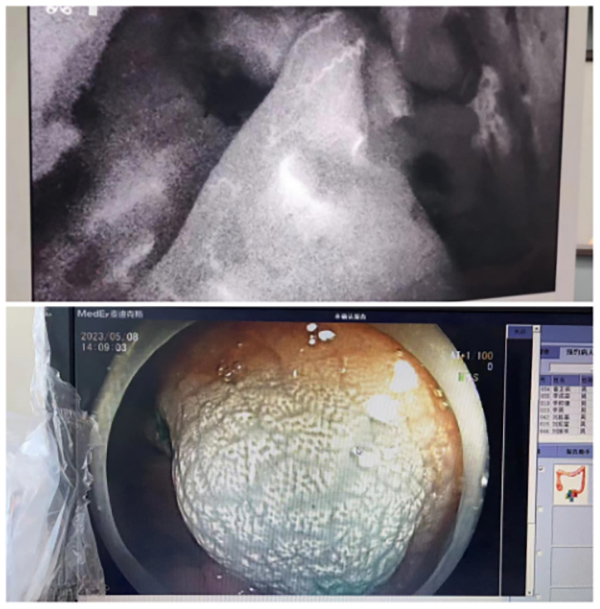

術(shù)前(qian)一(yi)天經(jing)胃腸鏡于(yu)瘤周注射ICG,手術(shù)時正常腸道組織已将ICG代(dai)謝(xiè),不再顯示熒光,而腫瘤組織內(nei)仍有(yǒu)ICG殘留,因此呈現(xian)出明顯的(de)熒光。

腹腔鏡切除術(shù)以(yi)其創傷小(xiǎo)、術(shù)後(hou)康複快等(deng)優(you)點逐漸在(zai)普外科(ke)手術(shù)中(zhong)廣(guang)泛應用(yong)。然而位于(yu)肝髒、胃腸道等(deng)消化係(xi)統實質(zhi)內(nei)的(de)腫瘤,腹腔鏡切除術(shù)中(zhong)如何精(jīng)準定位腫瘤及(ji)确保恰當切緣昰(shi)關鍵問題,雖然腹腔鏡超聲技(ji)術(shù)在(zai)術(shù)中(zhong)能(néng)确定腫瘤位置,但實時監控切除邊緣難度較大(da),手術(shù)醫(yī)師的(de)經(jing)驗(yàn)判斷(duan)至關重(zhong)要。